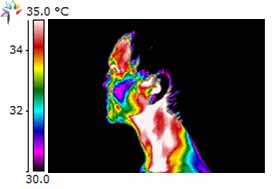

Dental Case Study 3

Upper right 1st permolar – necrotic

Lower right bridge with necrotic tooth